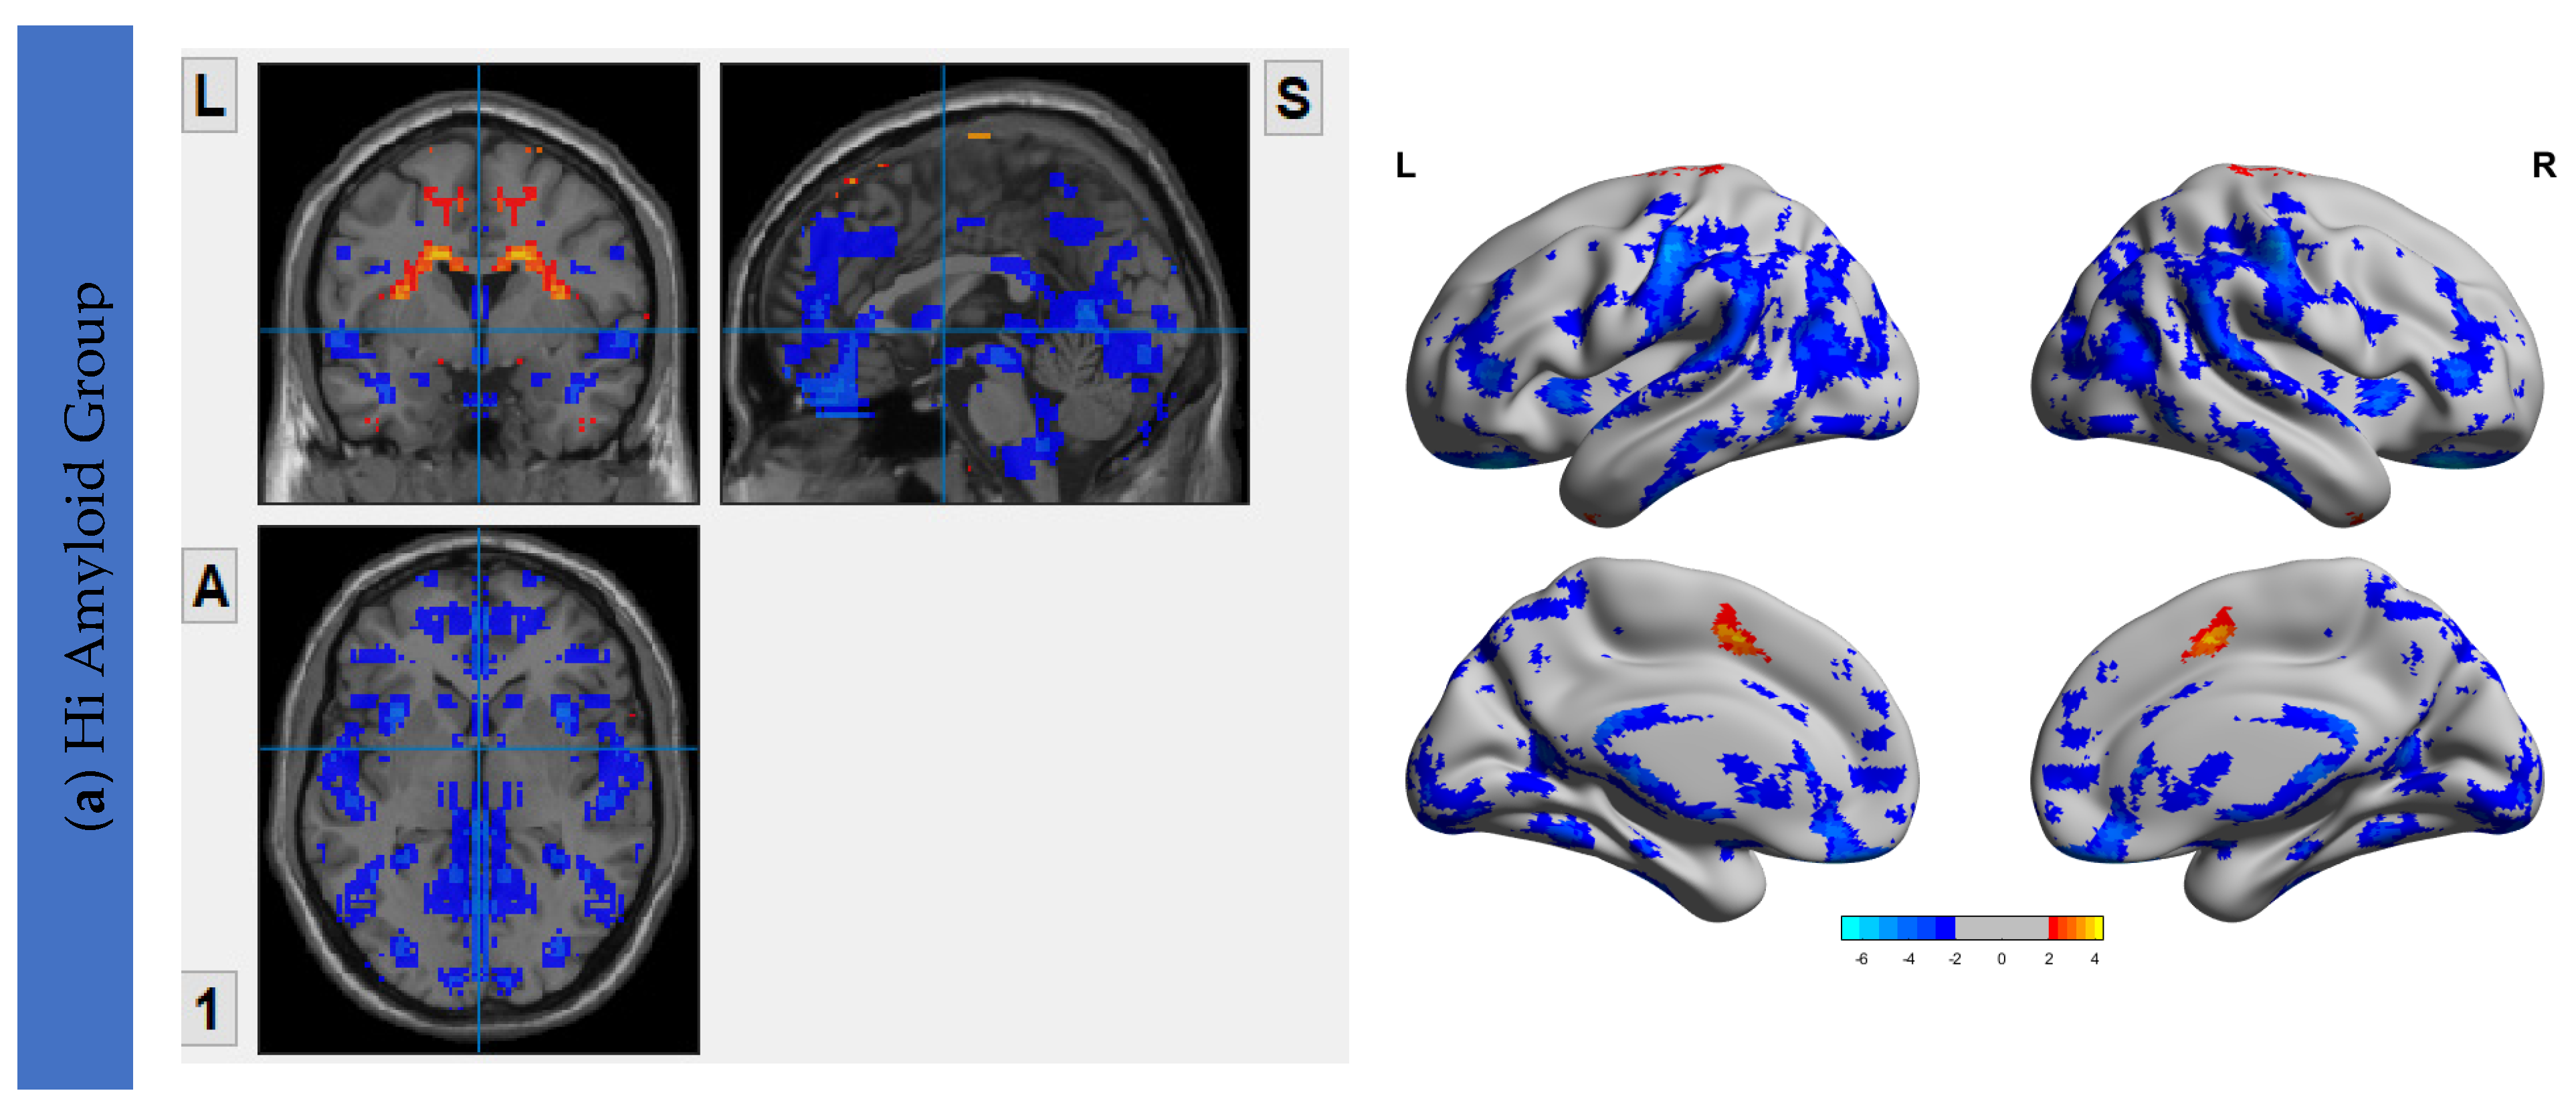

The VMHC maps for the HiAmy and LowAmy groups when compared to HC were showed in Figure 2. For the HiAmy group, the VMHC maps showed reduced functional connectivity in most regions in DMN, CEN, SRN and SMN, except in regions of salience network, including anterior insular, anterior cingulate gyrus, putamen, pallidum, caudate and amygdala. While for LowAmy group, the VMHC maps showed increased functional connectivity in the precentral gyrus, superior frontal gyrus, inferior frontal operculum, rolandic operculum, supplementary motor area, anterior insular, middle cingulate and caudate.

Figure 2.

VMHC Maps showing interhemispheric functional connectivity (IFC) of HiAmy and LowAmy groups when compared to HC. (a) showed Voxel-wise two-sample t-tests of VMHC maps from HiAmy when compared to HC. (b) showed Voxel-wise two-sample t-tests of VMHC maps from LowAmy when compared to HC. All comparisons were adjusted for age, sex, and total intracranial volume, with Gaussian random field correction. The significance threshold at the voxel level was set at p < 0.01; and at cluster level was set at p < 0.05. The blue and red colors illustrate significant t values according to the scale on the right. VMHC: Voxel Mirrored Homotopic Connectivity. HC: Health Control. HiAmy: Patient group with global SUVr > 0.62. LowAmy: Patient group with global SUVc < 0.62.